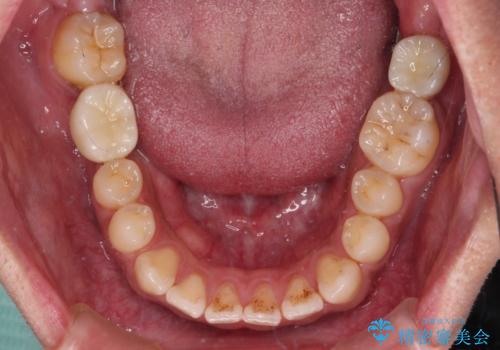

- ソーシャルメディアでのゲームに夢中になっている最中に車と接触し、前歯の抜歯を余儀なくされた患者様です。

初診時では前歯が保存できる可能性も模索しましたが、損傷が激しく3歯を抜去することとなりました。

保存となった隣在歯も神経が失活していており、補綴治療が必要であったので、オールセラミッククラウンにて補綴治療することとしました。

奥歯には元々欠損があり、欠損に伴う咬合不正も認められたため、部分矯正を行った上でインプラント補綴治療も行うこととしました。